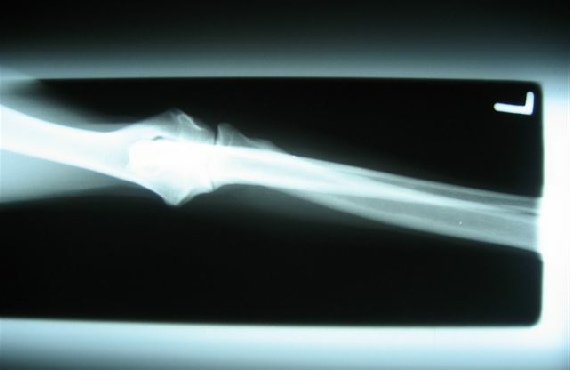

HD / ED RÖNTGENBILDER VON FACE

26.08.08 bekam ich eine Narkose (das fand ich gar nicht toll !!) , aber scheinbar sind diese Röntgenbilder, über meine Hüft- und Ellenbogengelenke, die dann gemacht wurden, ziemlich wichtig.